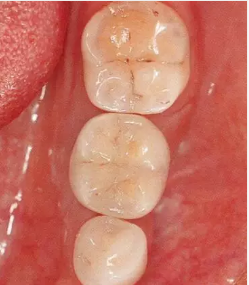

圖6-10 佩戴最終修復體時的(牙合)面照。